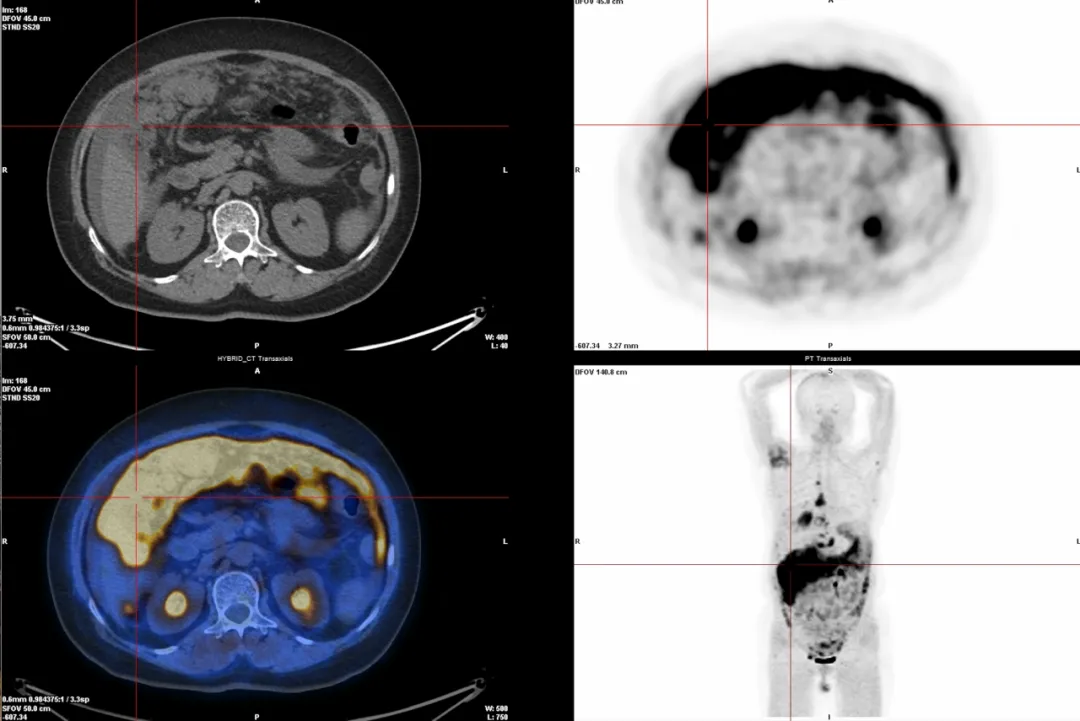

68Ga-PET/CT是一种更先进的癌症检查方法,比传统的“糖代谢”检查(18F-FDG PET/CT)更精准,尤其适合那些不太吸收糖分的肿瘤,比如某些神经内分泌瘤、前列腺癌等。68Ga-PET/CT就像“智能导弹”,能根据不同癌症的特点精准定位,比普通检查更准、更靠谱!

2.多种癌症检查(68Ga-FAPI):能检测很多种癌症,尤其是肝癌、胃肠印戒细胞癌、腹膜转移癌等,因为它能精准找到肿瘤周围的特殊细胞(成纤维细胞)。

△腹膜转移癌